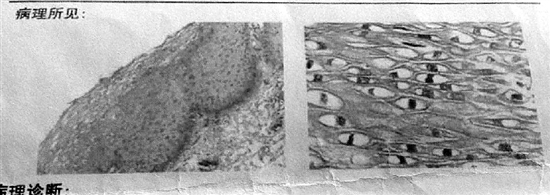

前后两个病理切片图像为何差异大?在迪安诊断工作的赵敏向记者解释,病理诊断的准确性,受很多因素影响,比如诊断医生的水平、取样的质量、切片是否切全等。“也有可能,即放、化疗后,细胞形态发生了变化,所以再次检查时看不到了。但可能性较小。”

在咨询杭州两家三甲医院的病理科医生时,对于第一张病理图像,两位医生的意见都一样:很典型,就是癌。但对比看了两张病理报告上的图像后,一位专家的想法与赵敏类似,另一位专家第一反应是,“不像一回事,这个会不会是别人的?”

他解释,第二张报告图像,看到的是类似鱼鳞的组织,跟张女士2015年的诊断相符;而第一张报告图像,更像腺癌。原来得了鳞癌,现在又得了腺癌,有这个可能性,但很小。倒是人为出错的可能性更大些。